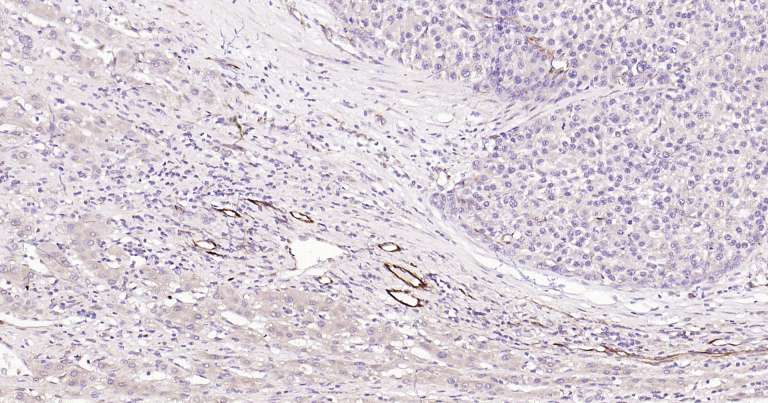

Immunohistochemical analysis of paraffin embedded human placenta tissue slide using IHC0291H (Human VEGFA IHC Kit).

Immunohistochemical analysis of paraffin embedded human hepatocellular carcinoma tissue slide using IHC0291H (Human VEGFA IHC Kit).